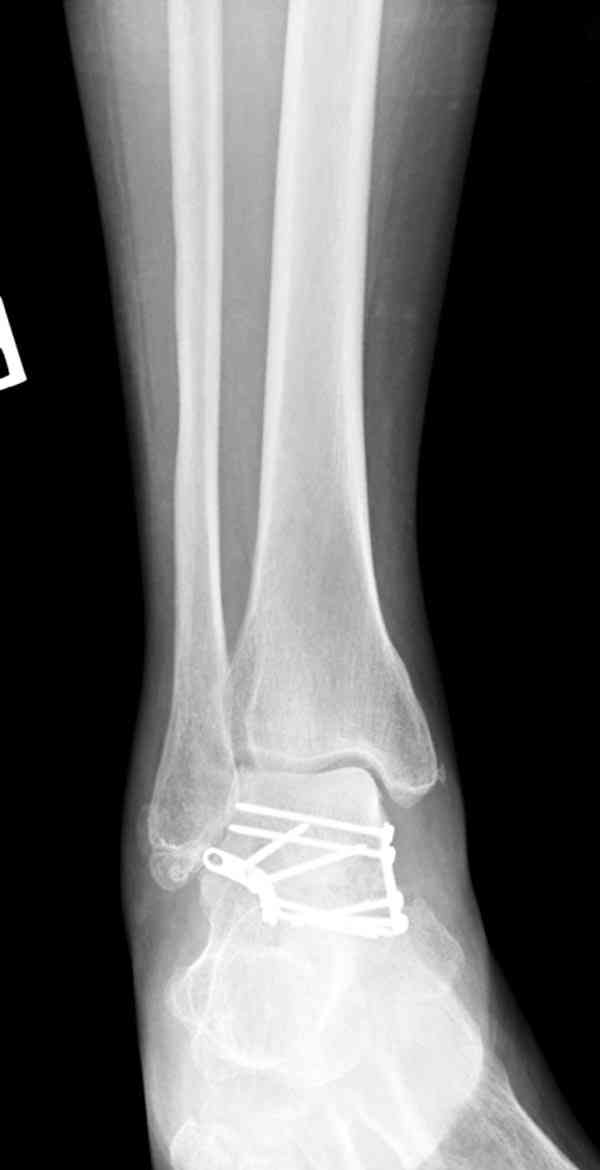

Решили не связываться с остеосинтезом, а сделать сразу берцово-пяточный блок. Снимки в приложении.

По завершении удлинения, наверно, заштифтуем.

Комментарии/критика приветствуются.